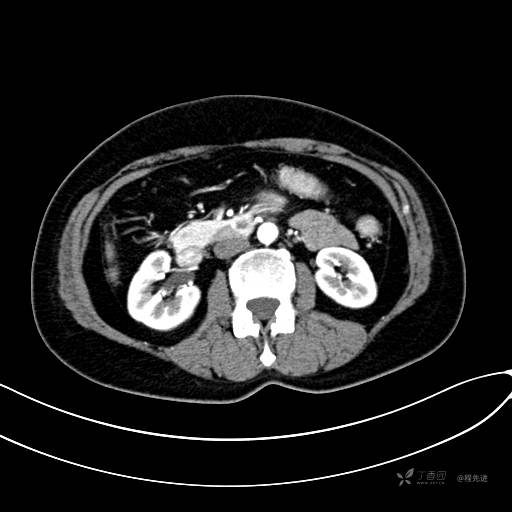

CT增强门脉期